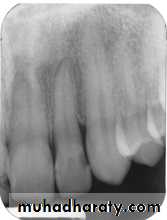

The bitewing radiograph is the view of choice for the evaluation of periodontal disease.

In addition to the periapical radiograph with paralleling technique could be used also, to evaluate the height of crestal bone is accurately recorded in relation to the tooth root.

Use of bisecting technique resulted in dimensional distortion of the bone due to the vertical angulation.

The normal alveolar crest lies 1 to 1.5 mm below the adjacent CEJs and forms a sharp angle with the lamina dura of the

adjacent tooth.

Between the anterior teeth the alveolar crest normally is pointed and well corticated.